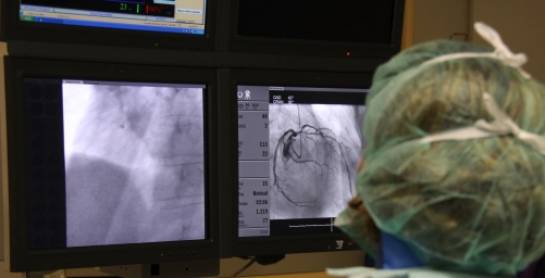

En el Instituto del Corazón Teknon contamos con tecnología de diagnóstico de última generación y podemos ofrecer los tratamientos más eficaces para solucionar los problemas de su corazón: angina de pecho, infarto de miocardio, lesiones de las válvulas cardiacas, insuficiencia cardíaca, arritmias, hipertensión arterial, etc.

Una historia clínica detallada y la realización de pruebas de diagnóstico serán claves para obtener una información completa sobre cómo resolver su problema cardiovascular, obteniendo información sobre la anatomía, la fisiología y la función del músculo cardíaco. En este sentido, las técnicas de diagnóstico en cardiología van desde el básico y tradicional electrocardiograma, todas las modalidades de ecocardiograma y las pruebas de esfuerzo, y las más modernas y nuevas técnicas como la Resonancia Magnética Cardíaca o el TAC Coronario DMD.